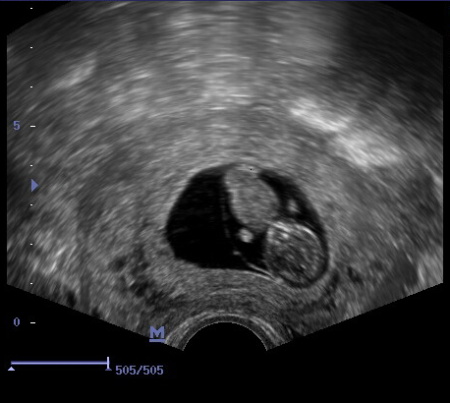

Celé těhotenství probíhalo v pořádku, první screening, test na cukrovku.. až se přiblížil 20tt a s ním druhý velký ultrazvuk. Byla jsem strašně nervózní a bála jsem se. Přijeli jsme do olomoucké fakultní nemocnice a čekali, až na nás přijde řada. Potom jsem skoro ani nebyla schopna dojít do ordinace. Při ultrazvuku jsem se paní doktorky pořád ptala na všechno možné, a když řekla, že je miminko v pořádku, začaly mi téct slzy štěstí. Mimo jiné jsme se dozvěděli, že opět čekáme chlapečka. Byl to nádherný pocit vědět, že je ten tvoreček uvnitř v pořádku a že má všechno, co má mít… Cestou zpět jsme začali přemýšlet nad jménem pro naše miminko, jména, která jsme měli vybraná pro Andílka, jsme už dát nechtěli, tak jsem nakonec rozhodnutí nechala na manželovi a ten vybral moc dobře.